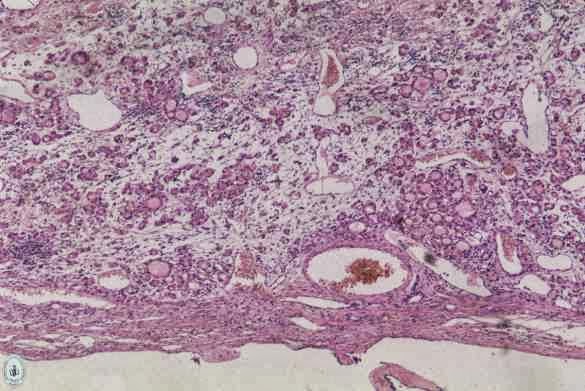

Estruma Ovárico .

Struma ovarii, hallazgos de patología tiroidea en el ovario .

Pathology Outlines - Struma ovarii .